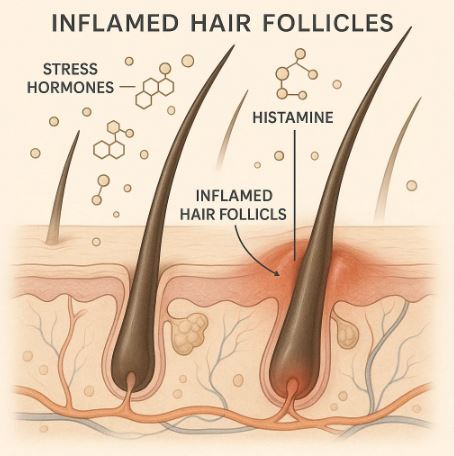

6. Lack of Sleep & Bad Breath

Lack of sleep leads to:

- Dry mouth → fewer antibacterial enzymes

- Higher cortisol → more inflammation

- Reduced saliva → bacteria overgrow

- Acidic mouth → gum pathogens thrive

That’s why people who slept 3–4 hours smell like they have gum disease next morning.

This doesn’t create disease overnight — but it encourages bacterial imbalance.